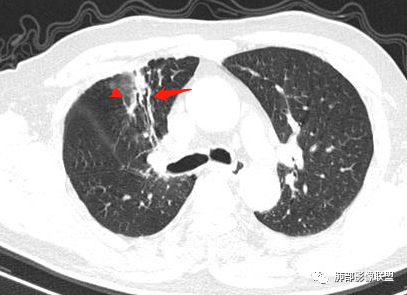

右肺上叶可见一团块影,边界清,有膨隆有凹陷,边缘可见毛刺,斜裂可见牵拉,不均匀强化,内可见液化,临近支气管未见明确阻塞,考虑腺癌可能,鉴别脓肿,结核等

右肺上叶团块,边缘毛糙,长索条,周围斑点影,邻近胸膜增厚,不均匀强化,其内小低密度灶边界清,考虑炎性肉芽肿,腺癌待排

右上胸廓缩小,叶间裂移位,尖段软组织影,前段支气管壁增厚,双上肺多发结节及条片影,增强后尖段软组织影内见多发低密度影,呈环状强化,考虑慢性肉芽肿,腺癌待排

老年男性,慢性病程,右肺上叶团块影,边界清晰,边缘毛刺,脐凹征,胸膜牵拉,不均匀强化,支气管壁增厚,考虑恶性,腺癌可能,鉴别肉芽肿、结核

男,69,反复咳嗽2年,加重3天入院,右肺上叶软组织密度肿块影,边界尚清晰,边缘见毛刺及胸膜牵拉,右肺上叶支气管壁增厚,增强扫描不均匀性强化,考虑腺癌可能,鉴别炎性病变。

右肺上叶见不规则团块,边缘清晰,周围可见长索条及斑片影,胸膜顶增厚,右侧斜裂部分增厚,右上肺体积略缩小,增强后不均匀强化,考虑炎性肉芽肿性病变,结核?鉴别腺癌

右肺上叶体积变小,见不规则实性病灶,边缘有平直,长软毛刺,邻近胸膜明显增厚,叶间胸膜牵拉上提、局部凹陷;病灶周围不干净,可见长索条影;近端支气管壁略增厚。增强后增强不均匀,有低密度坏死,间隔较厚。考虑慢性炎性肉芽肿,结核可能,鉴别腺癌。

右侧胸廓变小,右肺上叶团块,边缘毛糙,长索条,周围斑点影,邻近胸膜增厚,气管不规整,密度不均,不均匀强化,考虑炎性肉芽肿,腺癌待排。

右肺上叶尖后段不规则斑块病灶,后缘以斜裂为界,有边缘平直,周围见纤维及多发小卫星灶,邻近胸膜反应性增厚,纵隔胸膜下少量积液,同时右肺中叶内侧段支气管扭曲及牵引性扩张,周边见爬行征,胸廊入口变窄,纵隔未见淋巴结肿大,综合上述慢性炎性肉芽肿,结核可能性大,支气管镜肺泡灌洗!